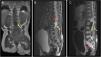

We present the case of a girl aged 2 years brought in for evaluation of lower back dimples and spinal hemangioma diagnosed at birth. She presented with progressive paraparesis with onset 2 months prior, muscle atrophy in the lower extremities, constipation and a tendency to urinary retention and a bulging mass under the hemangioma. The magnetic resonance imaging (MRI) scan showed a large intraspinal mass around the conus medullaris extending into the presacral space with cystic lesions and heterogeneous enhancement (Fig. 1). The complete blood count was normal, with negative results for serum alfa-fetoprotein β-HCG.

Preoperative MRI. (A) T1-weighted image, coronal view: hypointense intraspinal mass (yellow arrow). (B) T2-weighted image, sagittal view, hyperintense intraspinal mass at level of conus medullaris (yellow arrow). Notice the hyperintense signal associated with the large fluid collection in the distal portion of the spine (red arrow). (C) Post-gadolinium T1-weighted image, sagittal view: intradural mass with peripheral tracer uptake immediately below the conus medullaris (yellow arrow) extending to the presacral space (red arrow).